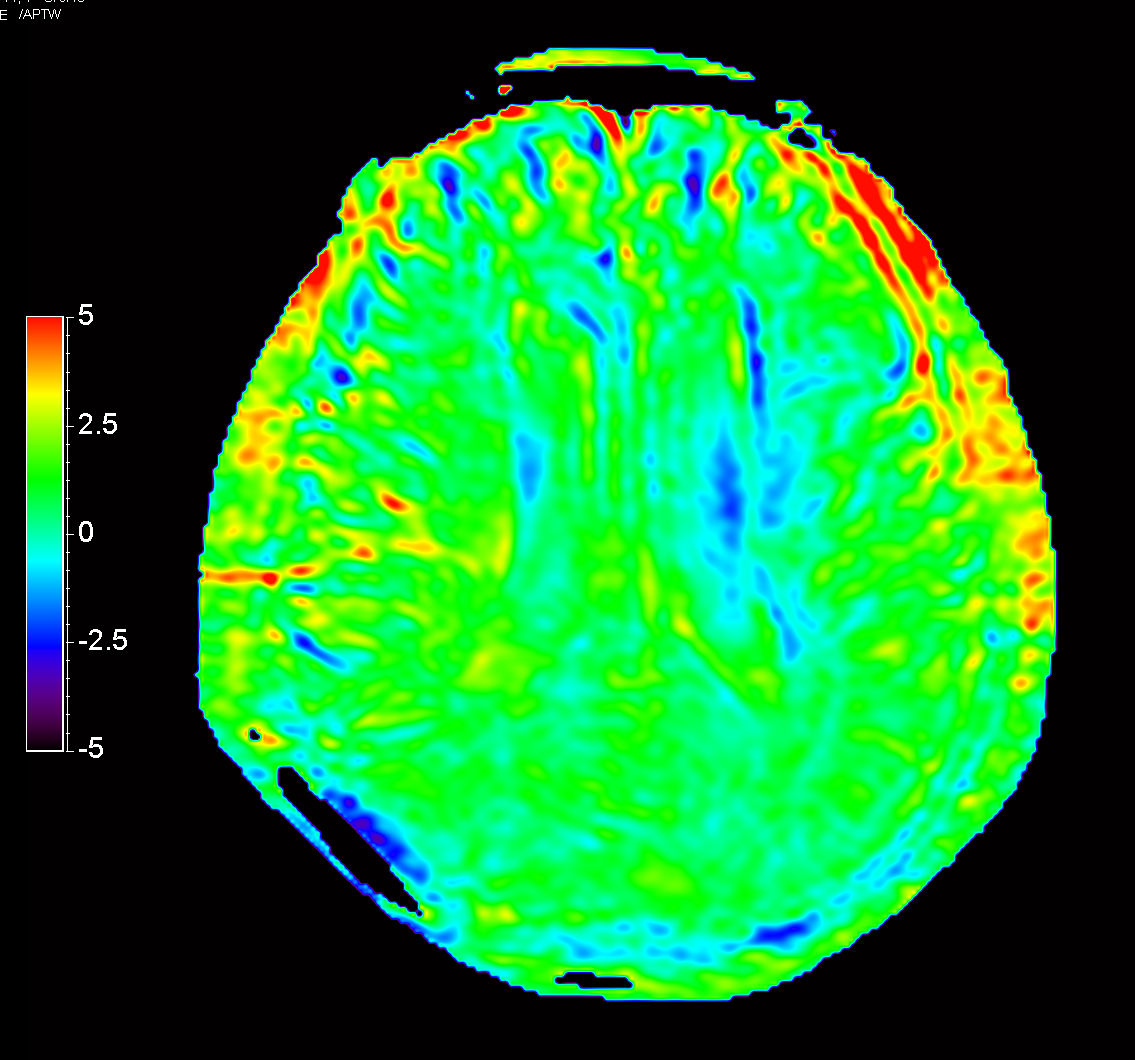

Patient with a small brain infarction. Compressed SENSE acceleration is used to speed up sequences while maintaining equal image quality. Three different diffusion methods are included; A fast 52 secs DWI EPI sequence, a high resolution DWI EPI sequence and a TSE based DWI sequence. A SWIp sequence is included offering high resolution 3D susceptibility weighted imaging to enhance contrast for deoxygenated (venous) blood or calcium deposits. 3D APT sequence is included providing contrast-free brain imaging, addressing the need for more confident diagnosis in brain neuro oncology by using the presence of endogenous cellular proteins to produce an MR signal. And a large FOV TOF MR Angiography sequence is included to check on brain vascular anatomy.

Axial 3D APT